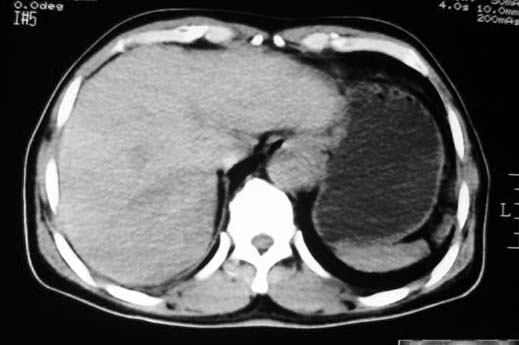

胃大弯侧,胃底与胃体交界处可见一圆形软组织肿块影,边缘较光整,内部密度较均匀

考虑胃的肿瘤或胰尾肿瘤,肝右叶后下段低密占位警惕转移。建议增强检查

病灶起源于胃壁向腔内外突出,边缘光整,内可见片状低密度区,考虑胃壁非上皮性肿瘤可能性大

病灶起源于胃壁向腔内外突出,边缘光整,内可见片状低密度区,考虑间质瘤可能性大,建议增强扫描。